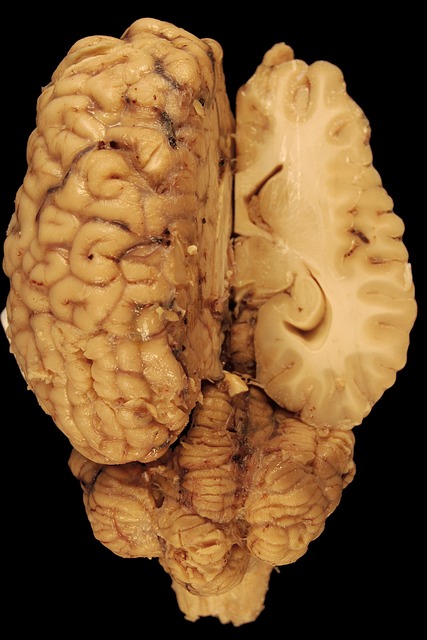

Brain Tumor

Brain tumor consists of cells that grows abnormally in the brain or it could grow near the brain. It can also occur in the brain tissue or near the brain tissue. This tumor most times can either be cancerous in nature or non-cancerous. And while some tumor grow slowly, some grow at a rapid speed.

Brain tumor has an impact on brain function and health if they have grown to the extent of pressing the surrounding tissues, nerves and blood vessels. There are primary tumors that develop in the brain, there are secondary tumors (metastatic brain tumor) that spread to the brain after forming in other parts of the body.